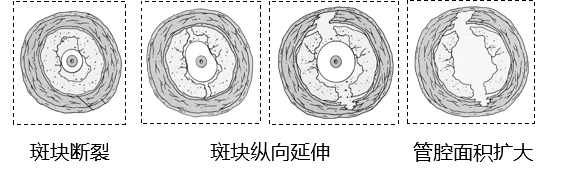

为了克服传统球囊的局限,适应更高的管腔准备要求,球囊技术本身也在不断进化。进化方向主要集中在避免夹层和提高管腔获得率。

★ 避免夹层的新技术与新球囊

递增性球囊扩张技术:采用由小到大的球囊进行序贯扩张,逐步打开管腔,减少对血管的创伤。

第一步:小直径球囊扩出通道。

第二步:稍大直径球囊使斑块纵向断开。

第三步:与靶血管1:1直径的球囊充分扩张,获得目标血管直径。

图:标准球囊在递增性扩张中应用